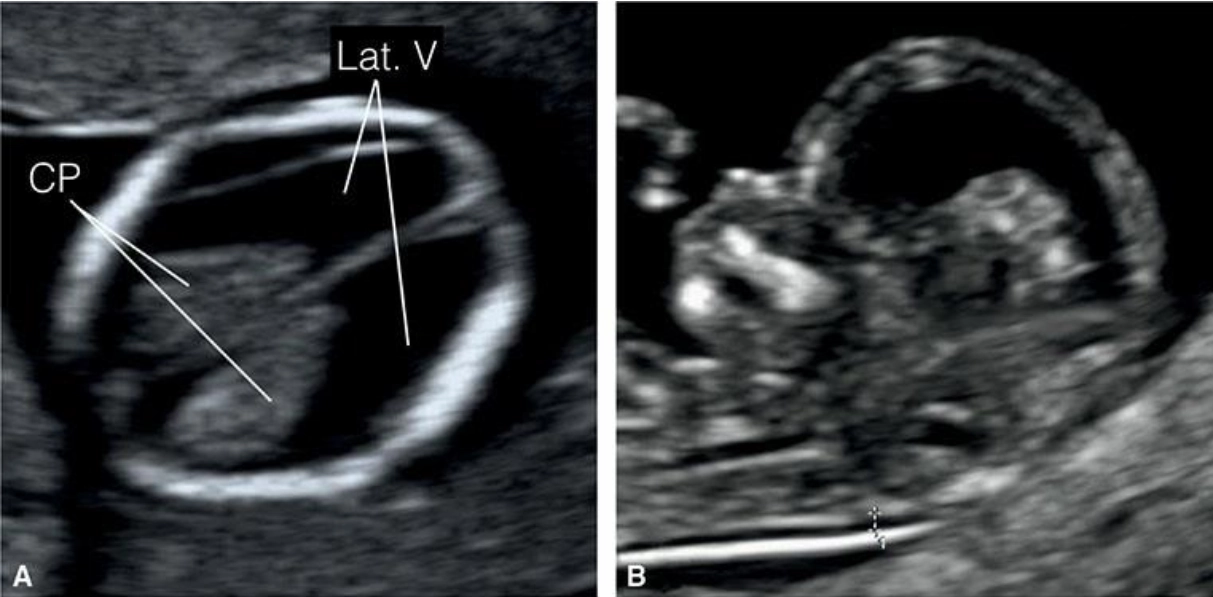

Giải phẫu bình thường hệ thần kinh trung ương thai quý I (Normal CNS anatomy in first trimester)